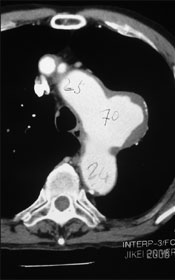

症例4

72歳 男性

【主 訴】

胸背部痛

【起始・経過】

平成18年7月CC出現。

平成18年8月当院紹介受診。

CAT scanにて弓部瘤の診断。

【既往歴】

CHF、高血圧(+) 喫煙歴(20本×30年)

【治療計画】

血管造影にて適応があればGore社TAG stent留置術

胸部CAT Scan所見